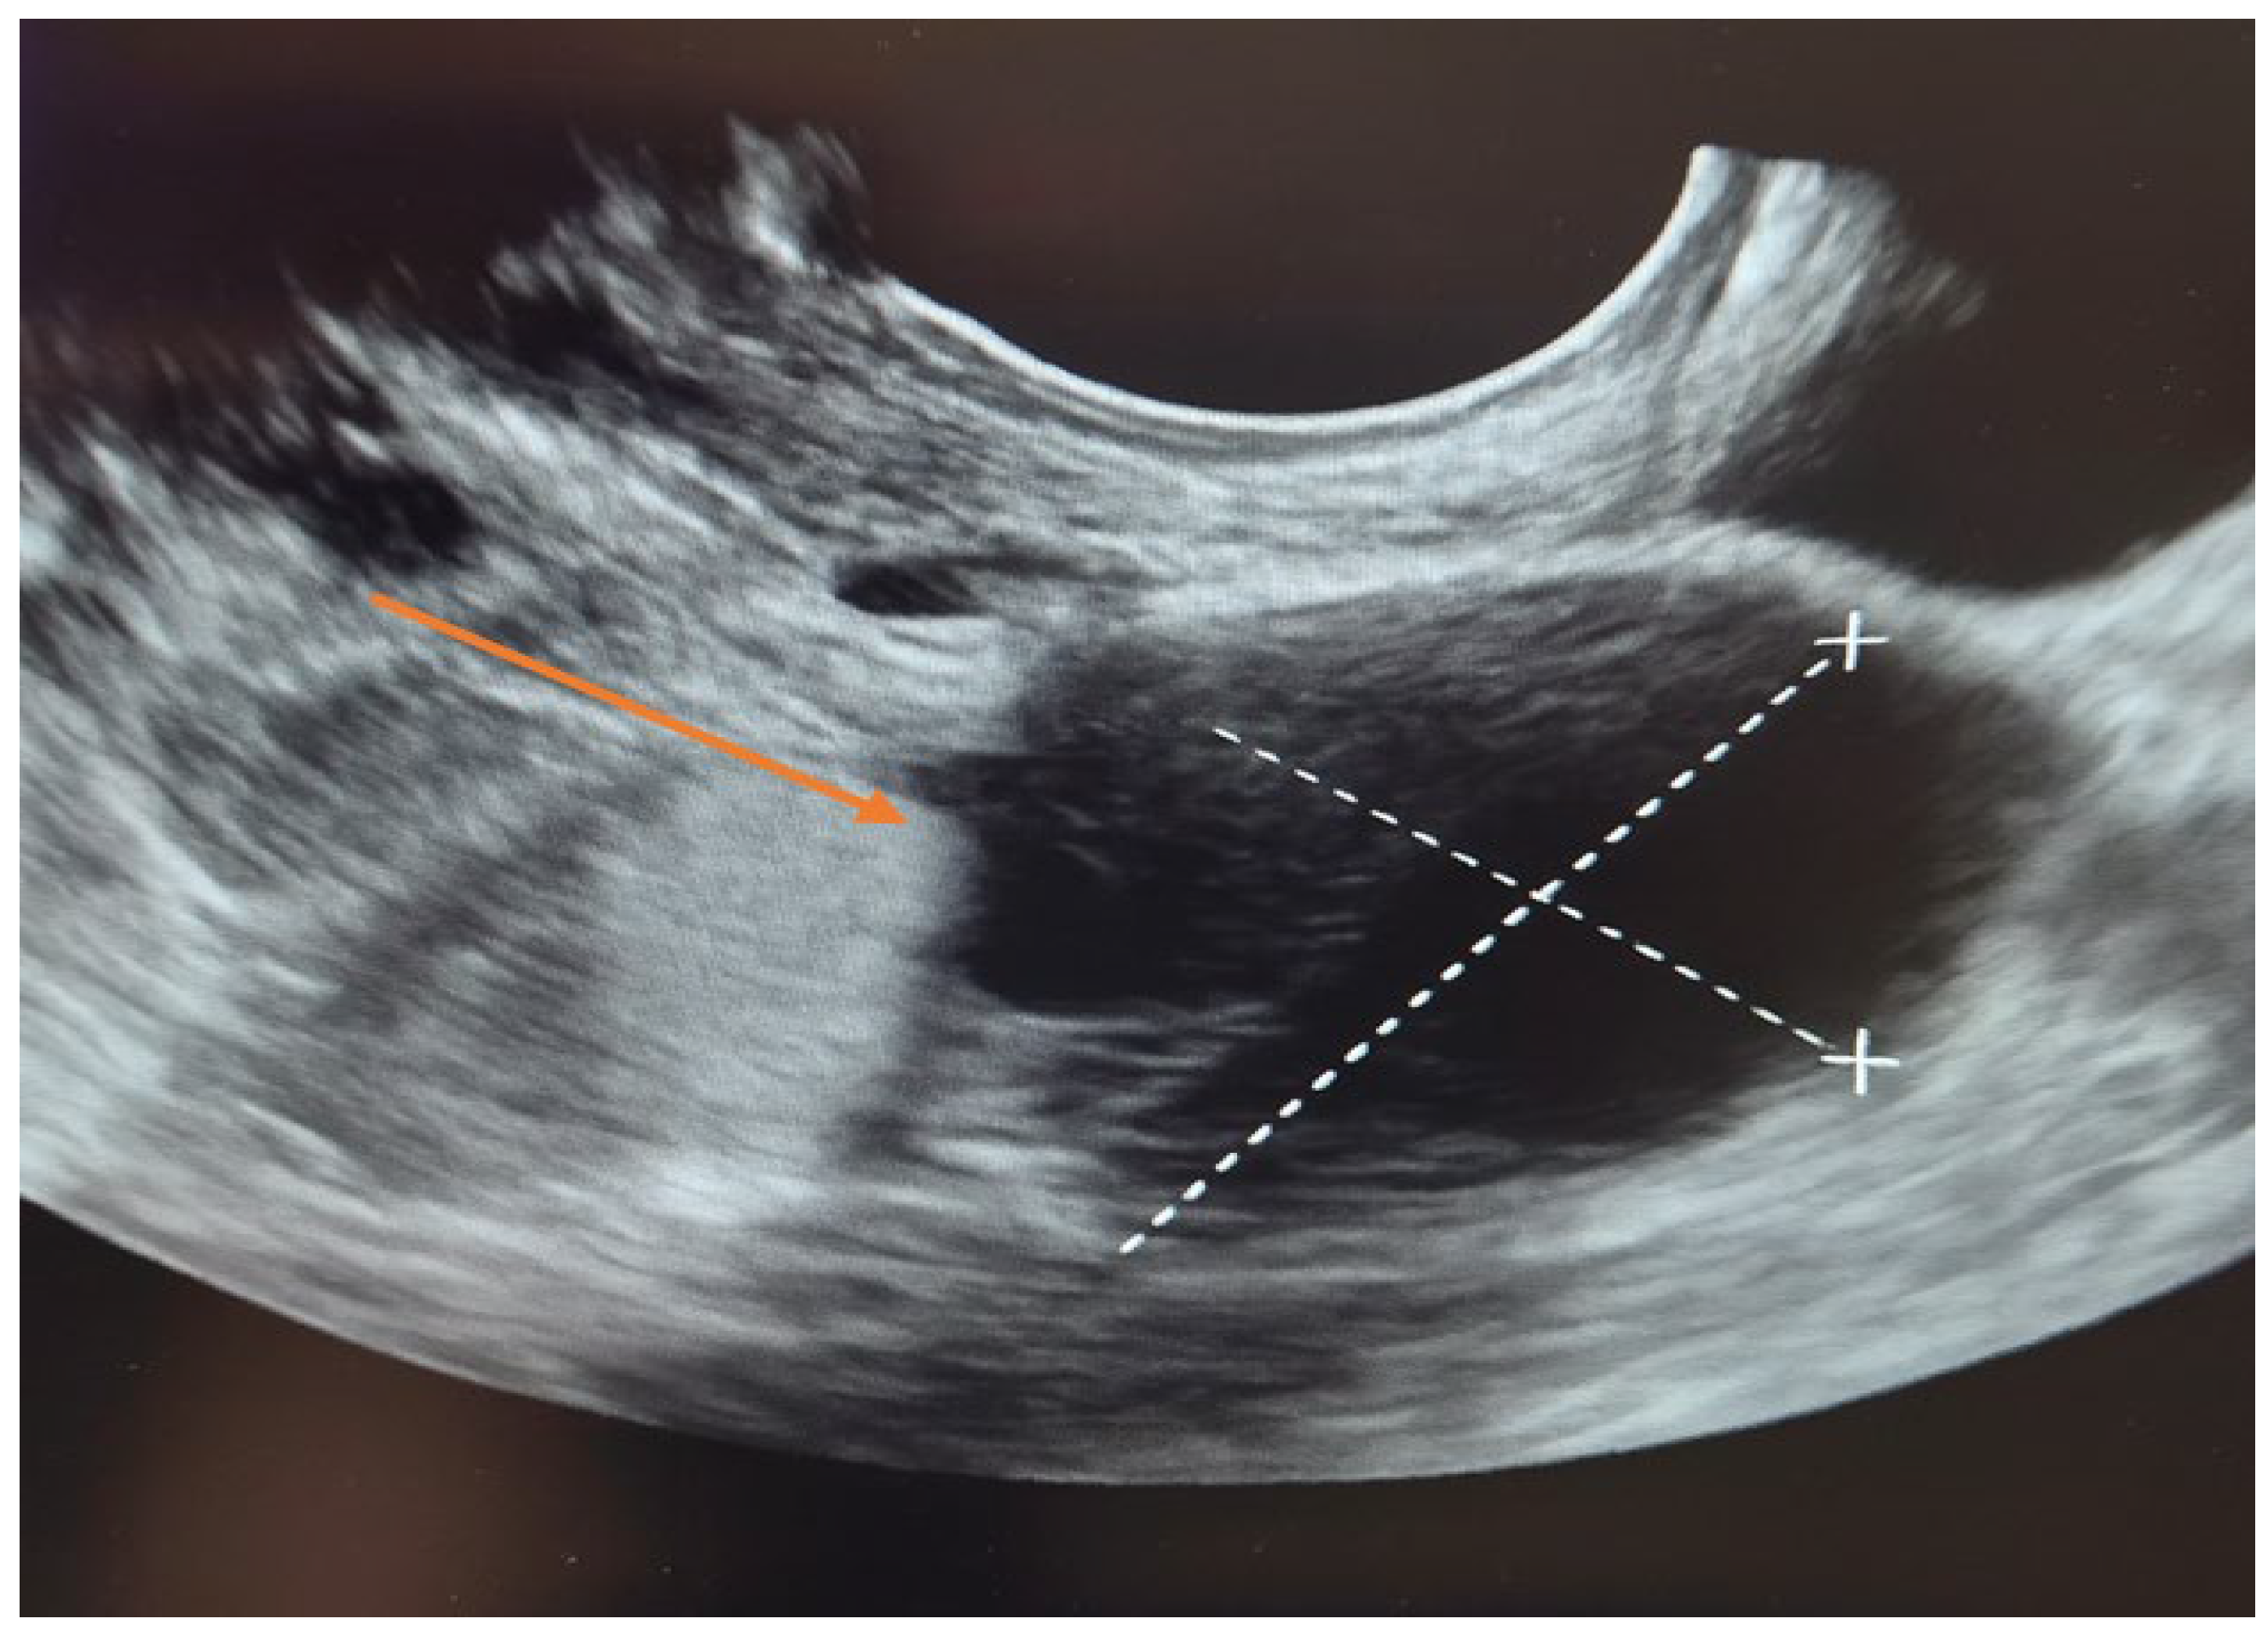

3.7. Histopathological Findings

Histopathological examination revealed a cystic lesion characterized by branching papillary projections of variable size. The papillae and intervening spaces were lined predominantly by simple to pseudostratified cuboidal or columnar epithelium, with only focal areas of stratification. Ciliated epithelial features were occasionally observed in a focal distribution. The underlying stroma consisted of a proliferation of bland spindle cells arranged mainly in fascicles. Importantly, no evidence of epithelial atypia or stromal invasion was identified (Figure 5 and Figure 6).

Figure 5. Papillary serous cystadenofibroma (H&E staining, ×40). The cystic wall is lined by simple to pseudostratified epithelium (black arrow), with underlying fibrous stroma (black asterisk).